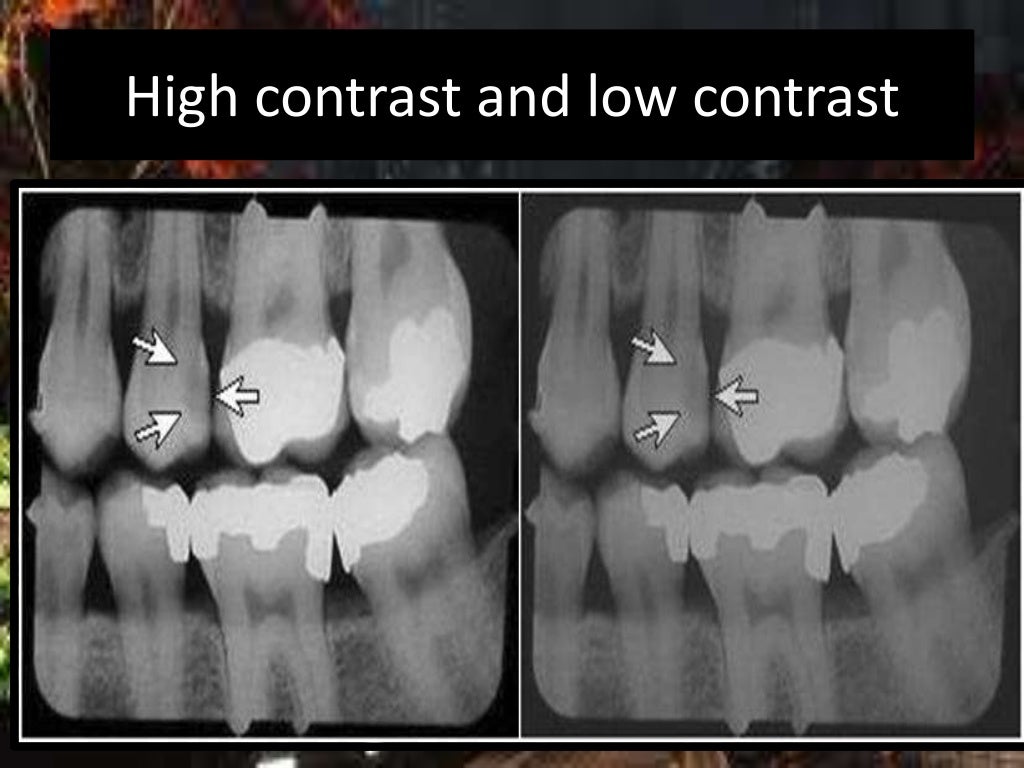

Dental Xray Errors . Learn how to avoid and correct common errors in intraoral radiography, such as placement, alignment, and angulation. Table 5 lists various errors that can occur with panoramic imaging. The ada recently released new guidance in jada on safety and regulatory aspects of radiography, which updates portions. The most common being improper exposure settings. Recognize items needing to be removed. It is important for the clinician to be able to understand errors when they occur and how to correct them. Improper time selection is the most likely error. Incorrect exposure can be caused by many factors; Are you or your team doing any of these, and if so, what can you do to correct your process?